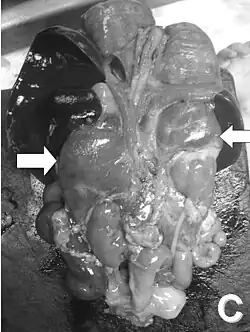

- guzy nadnerczy (40% pacjentów z postacią klasyczną).

- Odpowiednie zabiegi chirurgiczne[1][2] wykonane przez doświadczonego chirurga dziecięcego lub urologa dziecięcego pozwalają odtworzyć kobiece narządy płciowe u noworodków żeńskich.